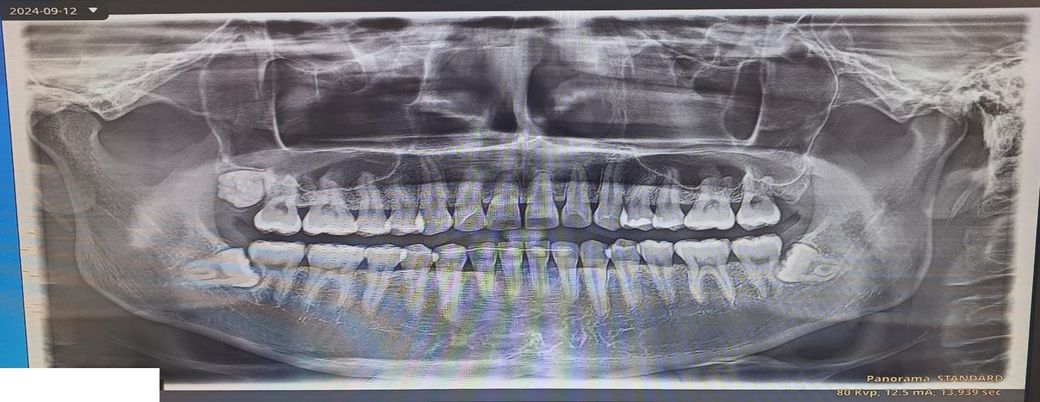

근데 제가 듣기론 사랑니가 바르게나면 안뽑아도 된다고 하는데 제 사랑니를 보시고 뽑아야 되는지 안뽑아도 되는지 어떻게 생각하시는지 말씀해주시면 너무 감사하겠습니다.

사랑니를 뽑는게 좋을까요 안뽑아도 될까요? 뽑아야한다면 어느사랑니를 뽑아야하는지 궁금합니다.

사진으로 봤을 경우에 사랑니는 완전히 매복이 되어 있는 것으로 보입니다. 치아가 완전히 매복이 되어 있고 문제를 발생시키지 않는다면 굳이 발치를 할 필요가 없습니다

아래 사랑니는 옆으로 누워 묻혀있는 수평매복 사랑니 입니다. 그냥두면 사랑니 바로앞 어금니를 상하게 하니 가능한 빨리 뽑는 것이 좋습니다.

3개다 바르게 나온 사랑니는 아닙니다 아래 사랑니 두개는 옆 어금니를 누르고 있는 양상으로 추후 정상 어금니의 치아뿌리 흡수 가능성도 있어서 예방적으로 발치를 하는것도 좋을 것 같습니다